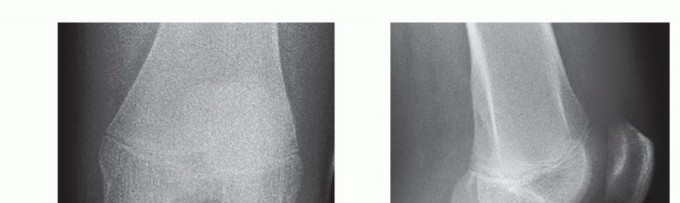

Standard anteroposterior (AP) and lateral views of the knee are usually adequate in making the diagnosis. These views help to define and identify the extent of bony injury.

A precise lateral radiograph is necessary as this is the best view to accurately assess fracture classification and fracture fragment position.

In lesions that are predominantly cartilaginous, radiographs may sometimes detect a small piece or a fleck of avulsed bone, which may be indicative of the avulsed osteochondral fragment, and underestimate the true size of the fracture fragment (FIG 4).

FIG 4 • AP (A) and lateral (B) radiographs of the knee showing a displaced tibial spine fracture (type III).*

AP and lateral radiographs of the knee are taken to document appropriate positioning of the screw and to document adequate reduction before closure (TECH FIG 2D,E).

Radiographs are taken to document adequate reduction of the fracture fragment.